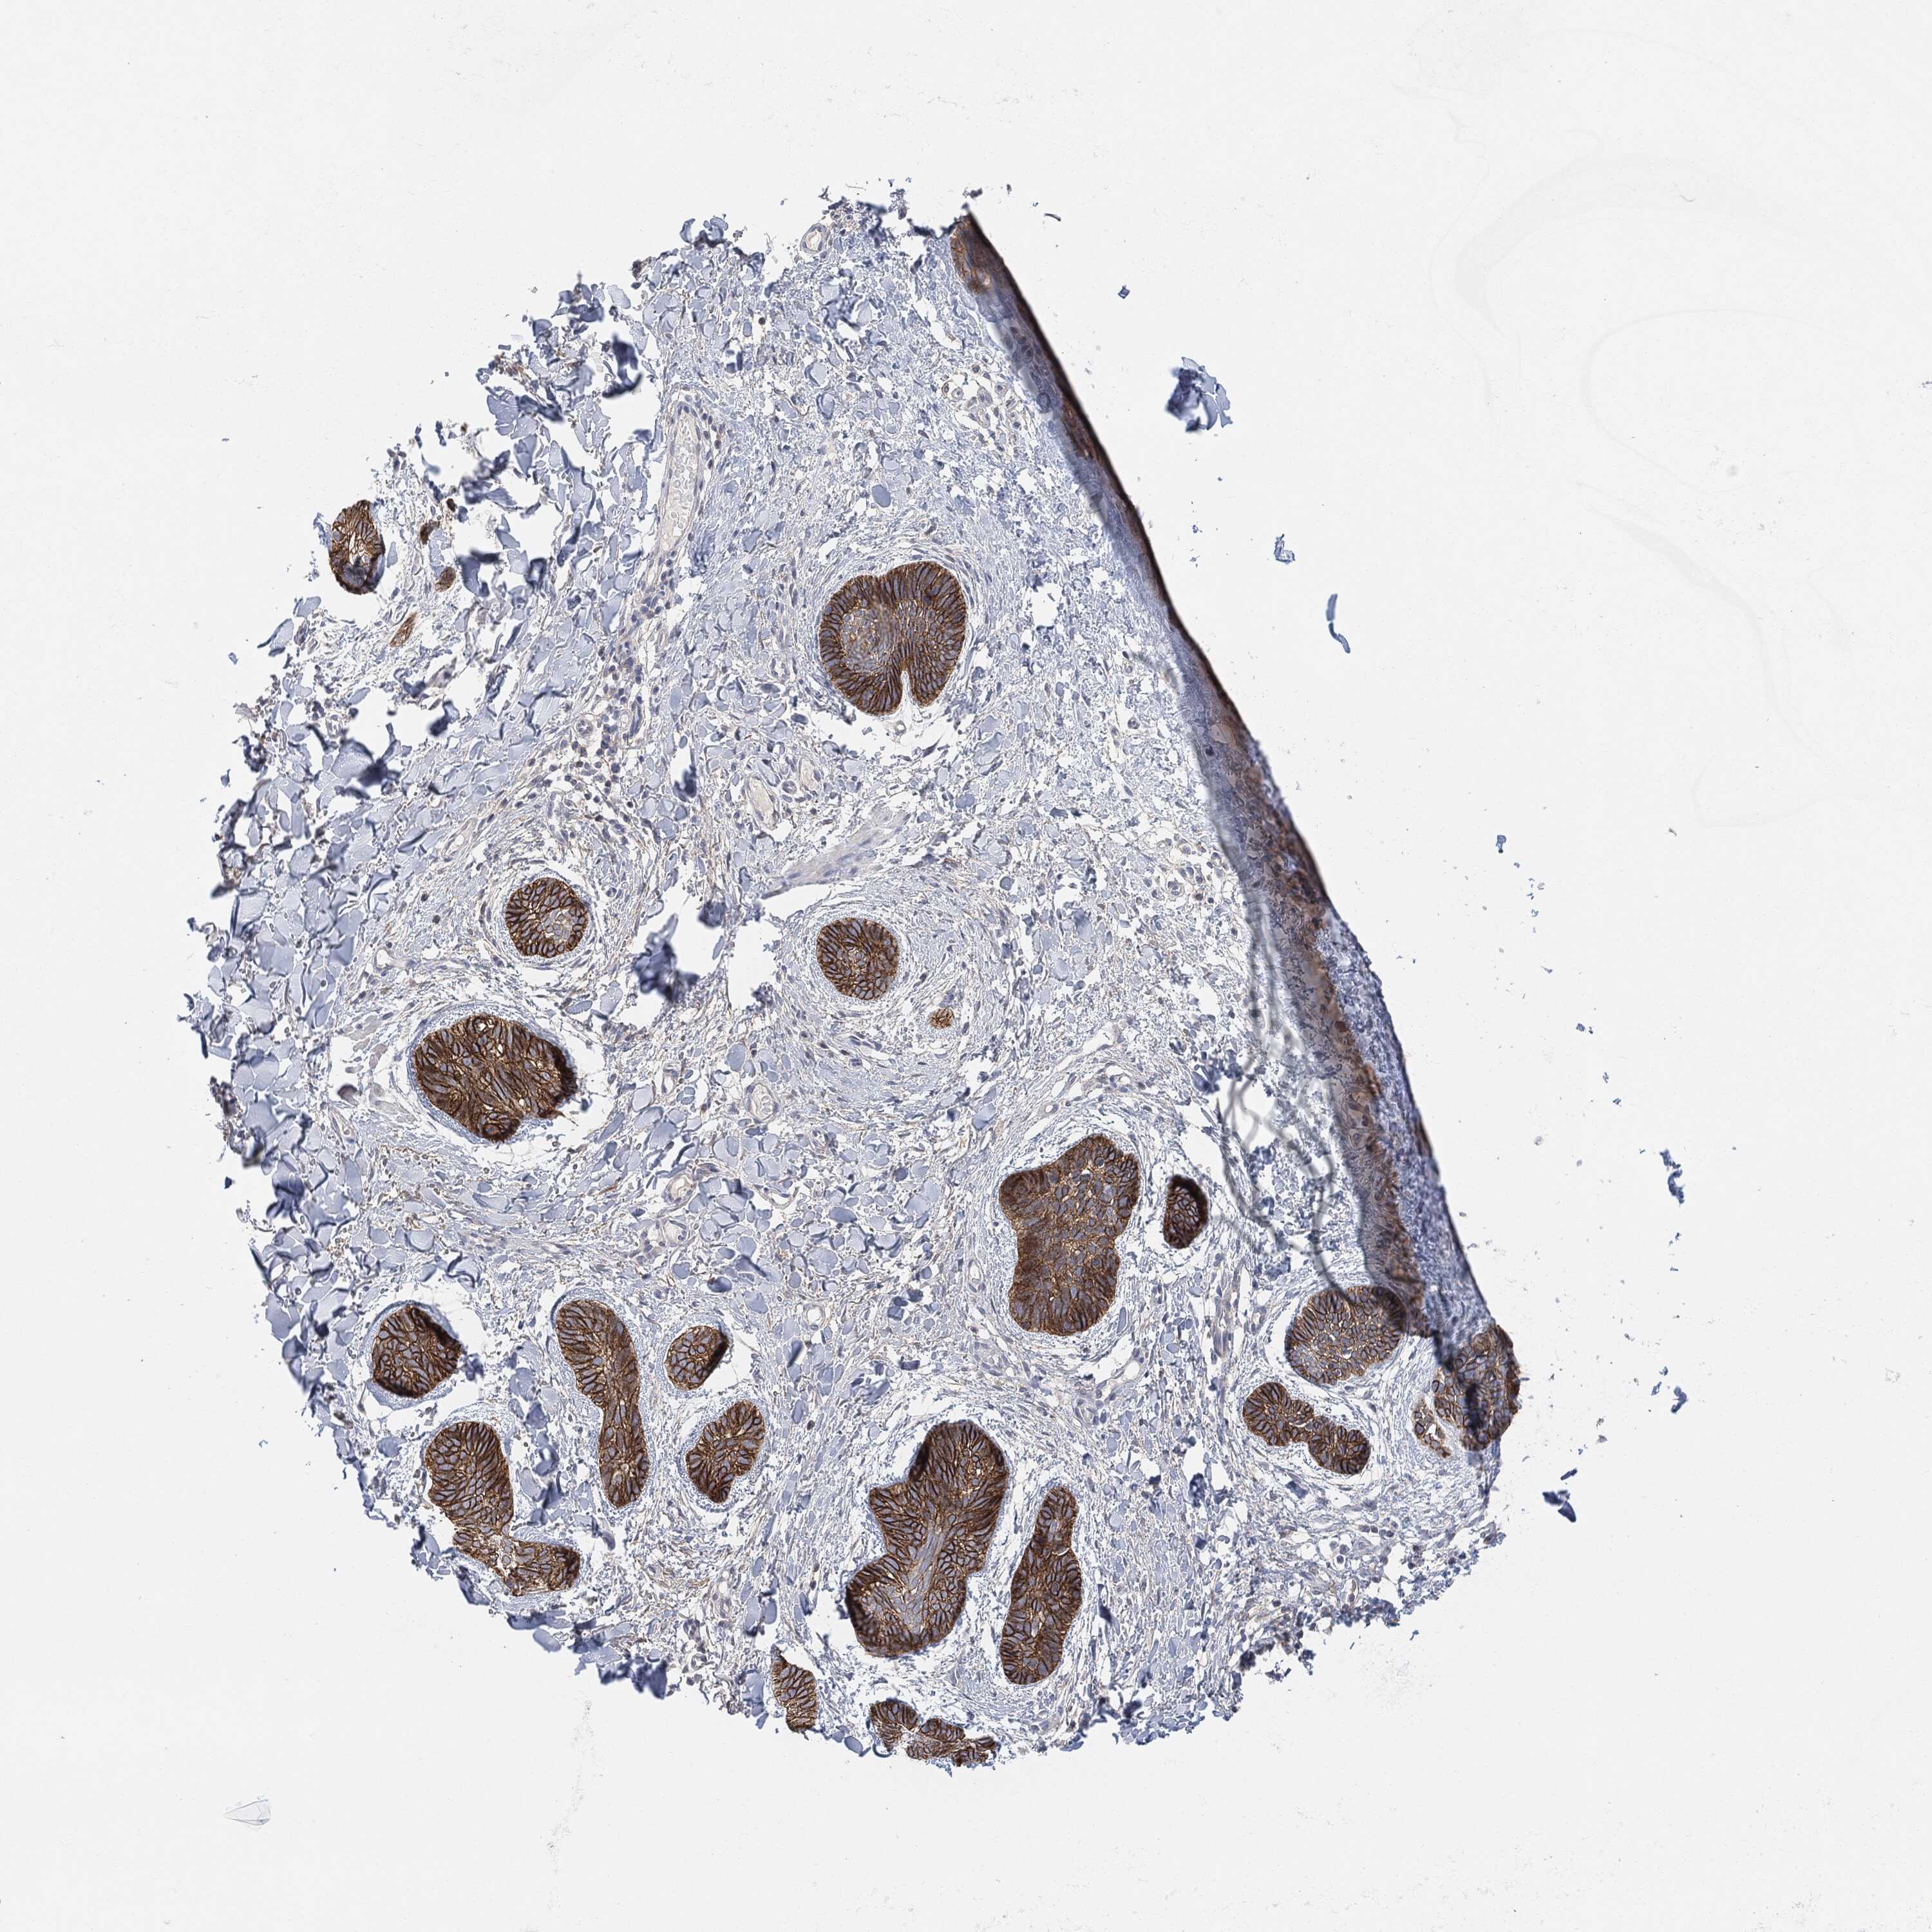

SKIN CANCER - Protein expressioni

A mouse-over function shows sample information and annotation data. Click on an image to view it in a full screen mode. Samples can be filtered based on level of antibody staining by selecting one or several of the following categories: high, medium, low and not detected. The assay and annotation is described here.

Antibody stainingi

Antibody staining in the annotated cell types in the current human tissue is reported as not detected, low, medium, or high, based on conventional immunohistochemistry profiling in selected tissues. This score is based on the combination of the staining intensity and fraction of stained cells.

Each image is clickable and will lead to virtual microscopy that enables deeper exploration of all samples and also displays staining intensity scores, fraction scores and subcellular localization as well as patient and tissue information for each sample.

HPA001200

Staining

High

Medium

Low

Not detected

Squamous cell carcinoma, NOS